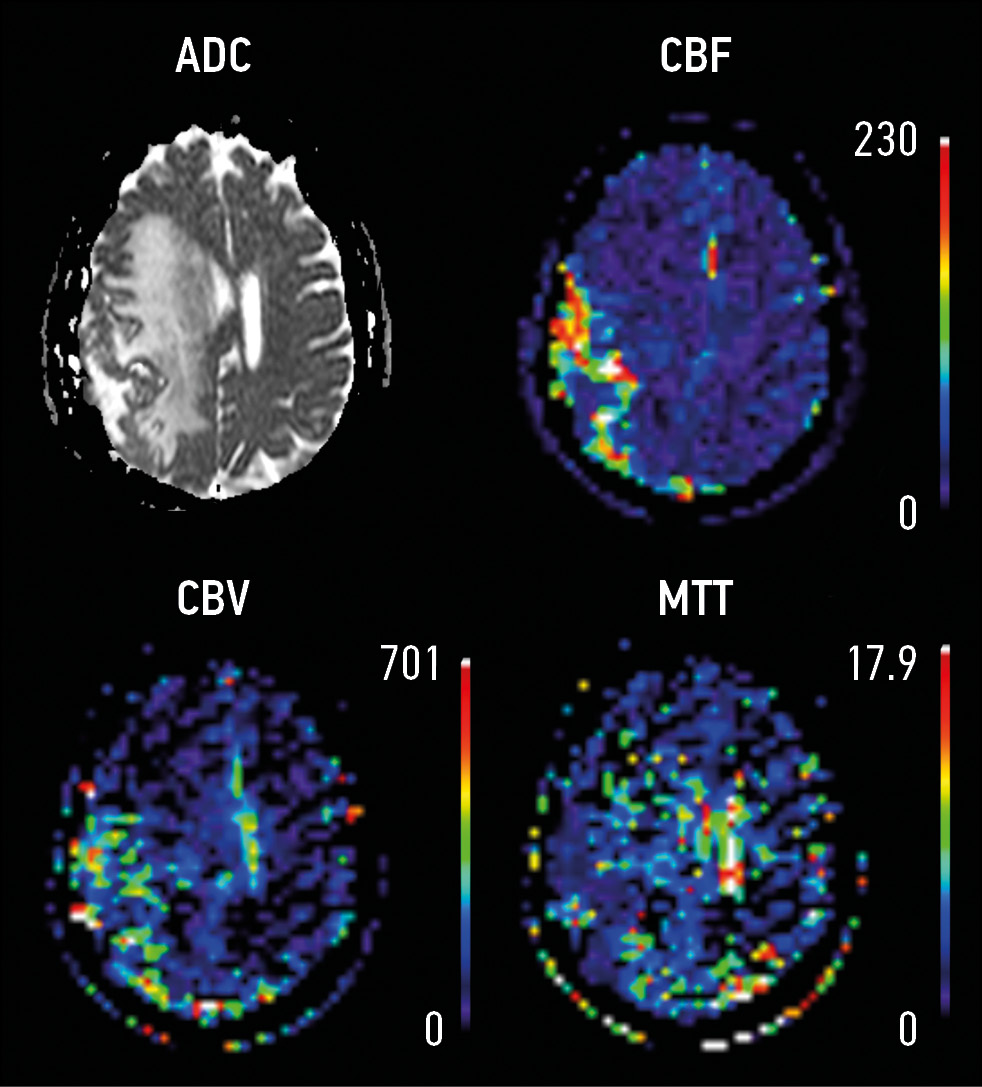

Материалы и методы. Ретроспективный анализ результатов исследований методом магнитно-резонансной томографии (1,5 Т) 156 пациентов с внемозговыми образованиями. Пациенты были разделены на 2 группы: (1) c наличием перифокальных изменений (n=106) и (2) внемозговым образованием без перифокальных изменений (n=50). В протокол сканирования были включены диффузионные и перфузионные последовательности. За зону интереса принимали (1) основной очаг и (2) зону перифокальных изменений. Выполнены измерения от основного очага и от зоны перифокальных изменений на картах измеряемого коэффициента диффузии, T2*-контрастной перфузии (DSС), проведен анализ серий динамического контрастирования (DCE).

Результаты. Максимальный размер основного очага (узла) поражения в 1-й группе составил 2,2 см (1,4; 4,3), во 2-й группе ― 1,2 см (0,9; 3,5); ограничение диффузии от основного очага поражения выявлено у 42 (39,6%) человек 1-й группы и у 7 (14%) ― 2-й. Максимальный размер перифокальных изменений в 1-й группе составил 2,85 см (1,5; 4,7). Ограничение диффузии от периферической зоны выявлено в 52 (49,1%) случаях. У пациентов 1-й группы с верифицированной менингиомой (n=66) путём многофакторного линейного регрессионного анализа выявлено, что максимальный размер основной зоны поражения увеличивал коэффициент объёмного кровотока (rCBF) от зоны перифокальных изменений в 3,3 раза (βcoef. 3,3, ДИ 1,27; 5,28; p=0,003), однако снижал показатель регионарного объёма крови (rCBV) в 4 раза (βcoef. 4, ДИ -7,46; -0,71; p=0,02).

Заключение. Перфузионные и диффузионные методы в сочетании с анатомическими последовательностями демонстрируют потенциал и могут выступать радиомическими маркерами при диагностике и лечении внемозговых образований. В дальнейшем наиболее перспективным выглядит выявление радиомических функциональных маркеров от зоны перифокальных изменений.